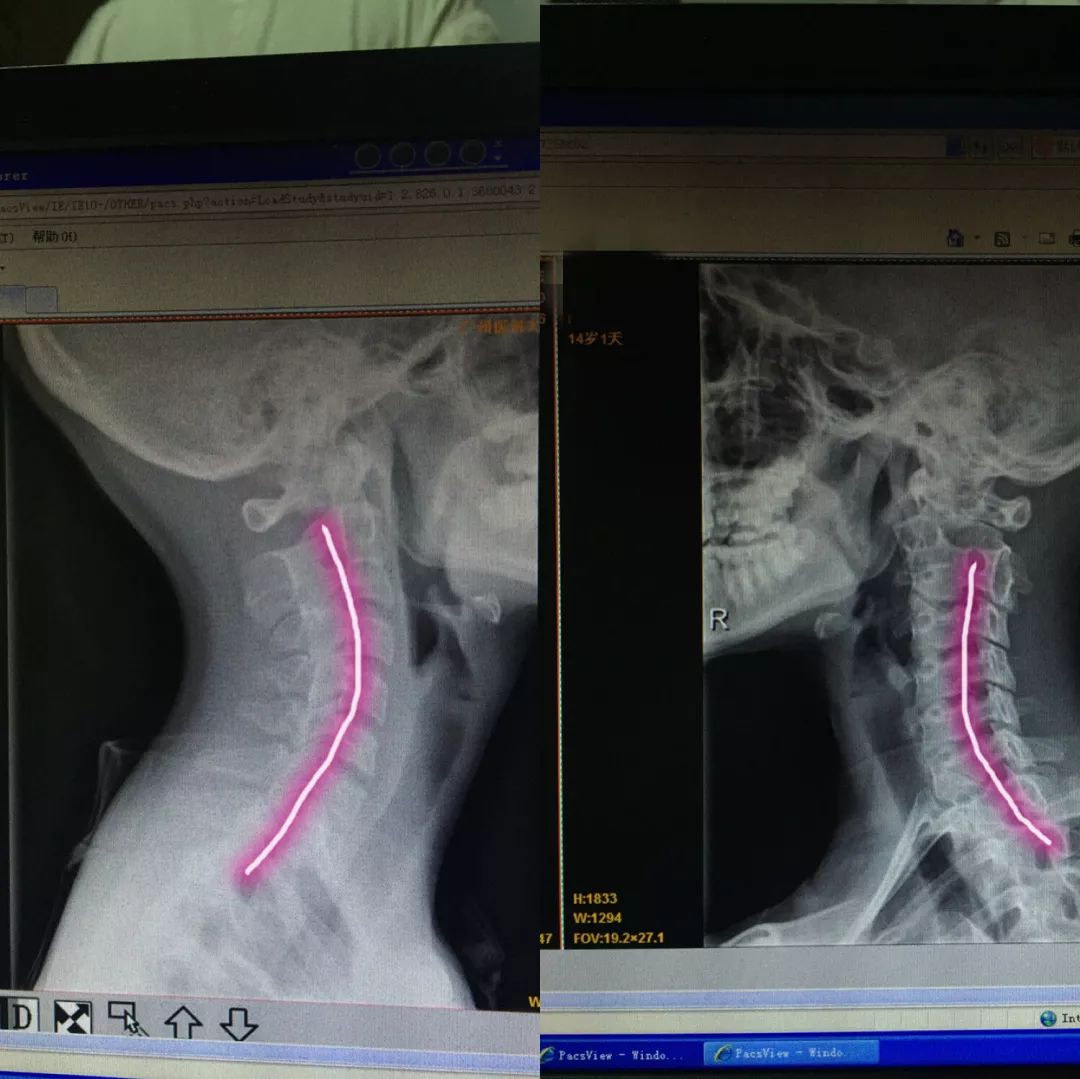

Aug 29, 16 · 康复保守治疗。 产生颈椎反弓的朋友不必过于慌张,90%颈椎反弓的患者可以通过康复治疗减轻甚至消除不良症状,改善颈椎曲度。 1、理疗 :传统的颈椎牵引、超短波、干扰电等理疗方式于炎症的消除、疼痛的控制有一定作用。Oct 11, 18 · 颈椎反弓目前非常常见,尤其见于初高中生。 以前颈椎反弓常见于6070岁的高龄的老年人,现在随着课业加重,很多学生也都出现颈椎反弓。 颈椎反弓不是完全无法治疗,治疗方法如下:1、Sep 12, 15 · 颈椎反弓怎么办?这是怎么引起的?4611阅读;

颈椎病盯上 低头族 16岁小嫚脖子反弓 青岛新闻网站 台东镇网 青岛本土生活服务门户